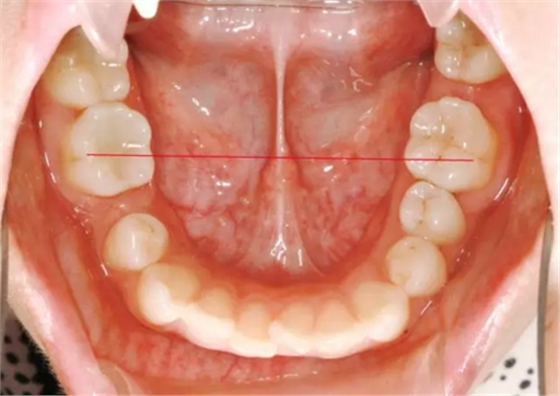

37,45缺失后,鄰牙近中移動(dòng)占據(jù)了部分牙位;患者要求減少治療費(fèi)用,不做種植修復(fù),那怎么協(xié)調(diào)右側(cè)的咬合關(guān)系?

15是根管治療過的牙齒,只好忍痛舍去......

在滿足功能的前提下,退而求其次...有時(shí)候,正畸醫(yī)生不得不妥協(xié)。